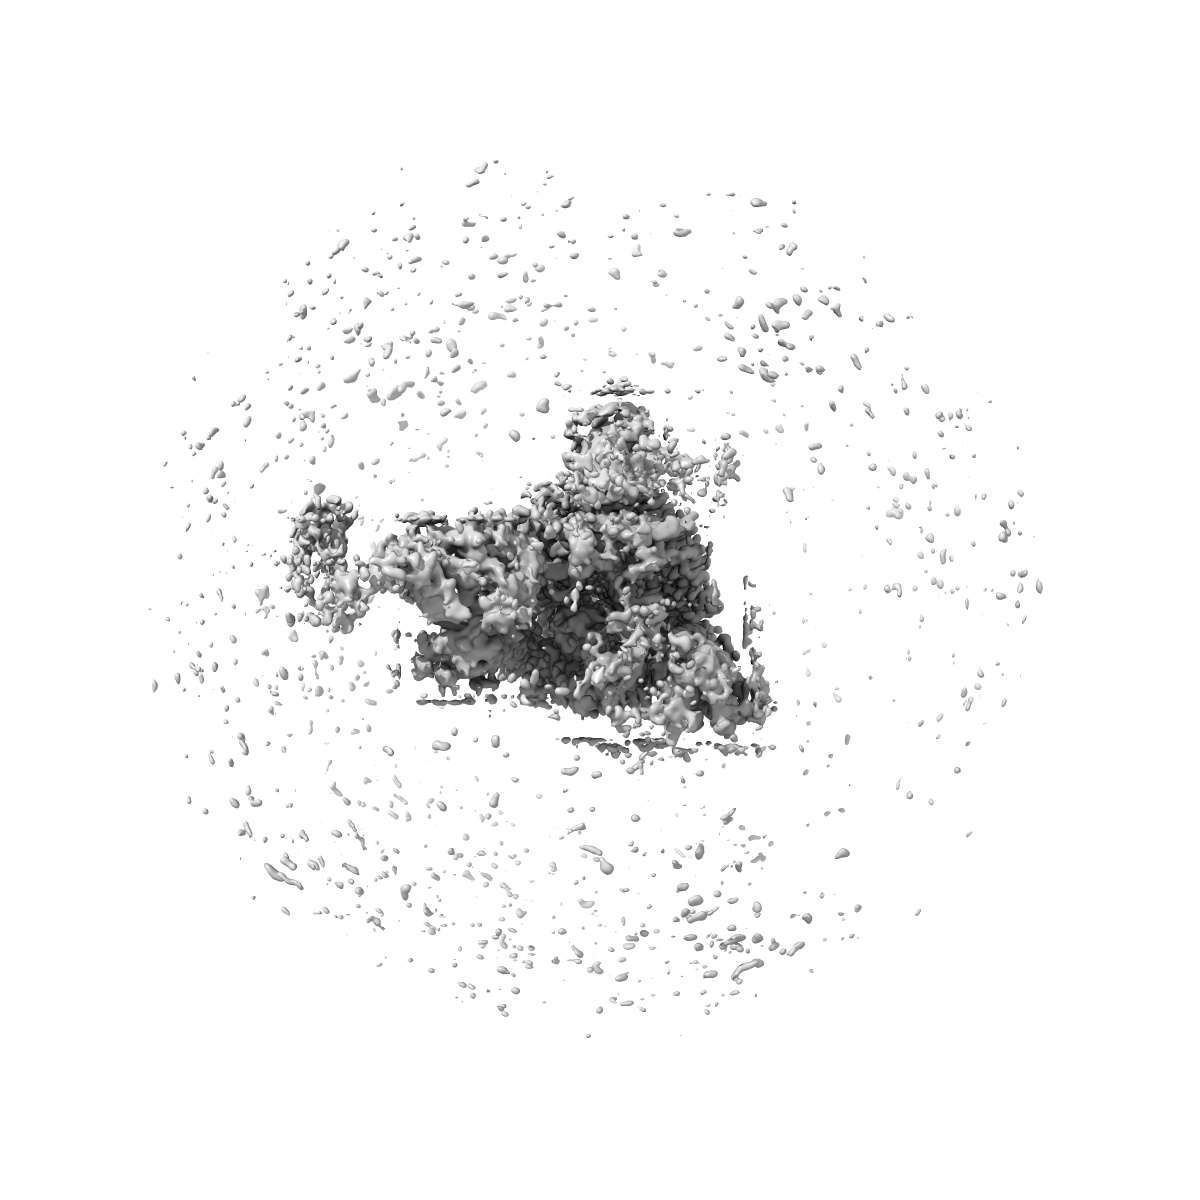

EMD-32683

SARS-CoV-2 Omicron Variant S Trimer complexed with one JMB2002 Fab

Single-particle3.18 Å

Sample: SARS-CoV-2 Omicron Variant S Trimer complexed with JMB2002 Fab